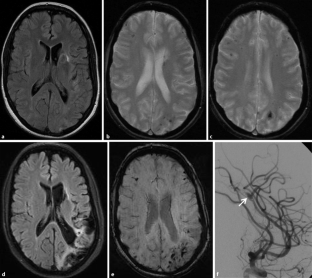

Abb. 4